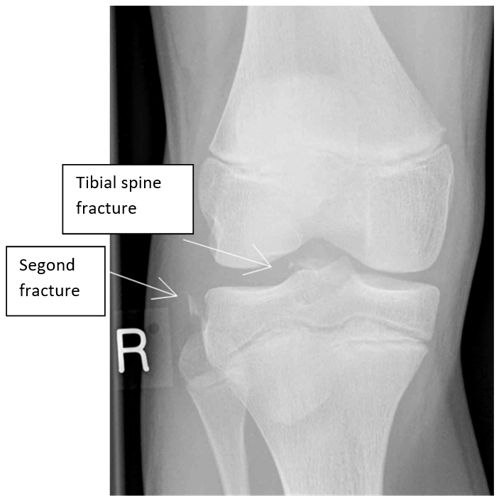

The XR should be reviewed for osteochondral fracture and/or lipohaemarthrosis, Segond or tibial spine fractures.